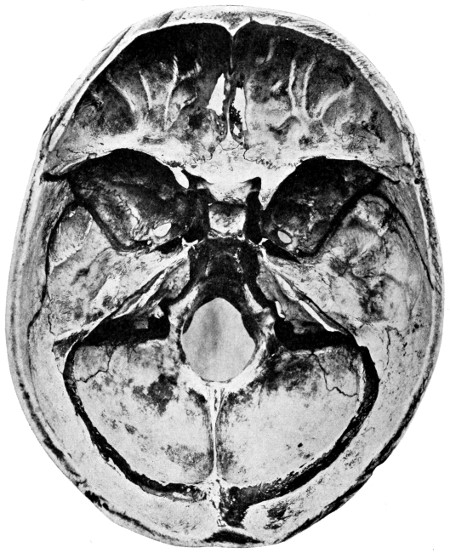

| 50 A and B. The inner aspect of the skull and the same seen on transillumination | 137 |

| 51. To illustrate compression of the brain as produced by an extra-dural hæmorrhage from the middle meningeal artery[x] | 141 |